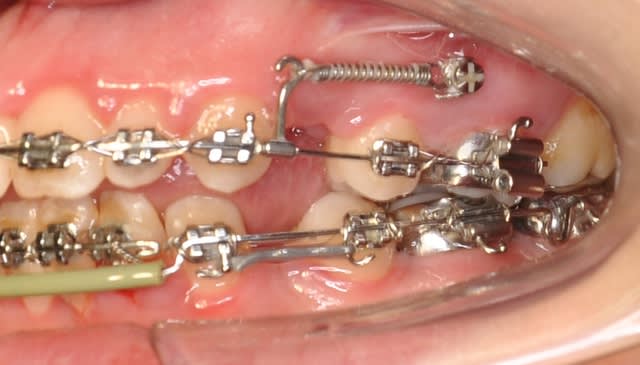

Je voulais que tu me dises ton avis sur cette mécanique

Dsc 0003 ccadd6 - Eugenol

Dsc 0007 rqtmo9 - Eugenol

Dsc 0004 b9m7js - Eugenol

Dsc 0005 s7pxry - Eugenol

Dsc 0006 piv60m - Eugenol